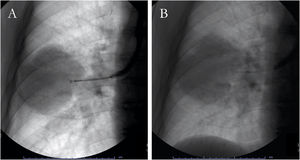

Peripheral lung lesionsA transbronchial biopsy is performed when the lesion cannot be directly assessed with the bronchoscope: it is wedged in the bronchus pertaining to the anatomical site of the lesion, and the closed forceps are pushed in the peripheral area of the lung, opened at 5...6...mm from the lesion and then closed to collect sample (Fig. 1A).6 Fluoroscopy guidance can improve the sensitivity in case of peripheral focal and diffuse cancer lesions.6,76,77 Observational studies have demonstrated that navigational methods (i.e., electromagnetic navigation bronchoscopy, radial probes ultrasounds, virtual bronchoscopy) and/or ultrathin instruments may increase the diagnostic yield of conventional, fluoroscopy-guided technique (77...84%).44,78...80